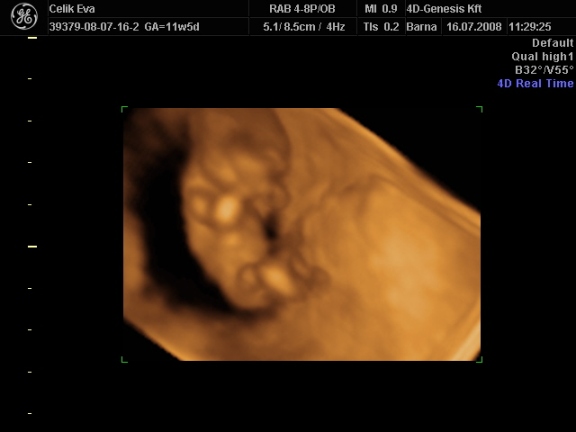

a képek:

3d-s babafotók:

Kép

ha megfürödtek a fiuk rakok fel 2d-s fütyis képeket is,meg egyet amin olyan édes arcocskája van :lol: